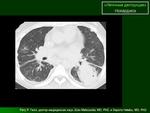

КТ. Карциноматозный лимфангит в сравнении с "нормальными лёгкими"

Наличие интерстициальных и узелковых изменений легких, в сочетании с патологией плевры, предполагает наличие лимфангического карциноматоза.

В пользу лимфангита еще преимущественное распространение в средних и нижних отделах, неструктурные корни, еще cuffing (разбухание?) стенки бронхов, подчеркнутость междолевых щелей (на боковом хорошо видно, средняя доля "выделена")